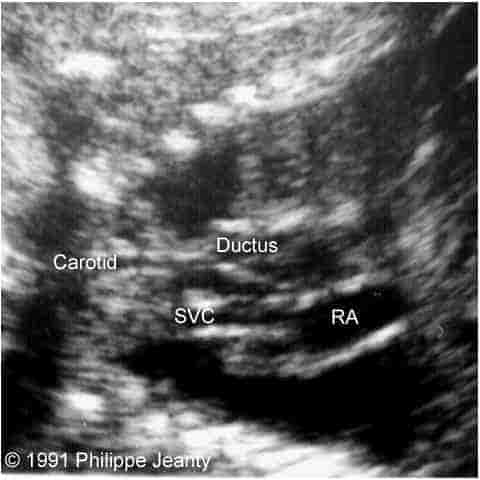

Figure 1: Top (left & right): Axial views of the base of the heart. The relationship between the superior vena cava (SVC), the ascending aorta (asc Ao) and the ductus is seen. Notice the larger size of the ductus compared to the aorta. Middle left: This section, just cephalad to the two previous, demonstrates the common carotids and the SVC. Middle right: Longitudinal section. The SVC is seen entering the right atrium (RA). The ascending aorta is between the SVC and the ductus. It does not connect with the ductus, and bifurcates into the common carotids. Bottom left: Similar view to the previous one. The conection between the ductus and the right ventricle (RV) is demonstrated. The ascending aorta lacks its normal curve towards the back and the left of the fetus. Bottom right: Thickened neck tissue with small cystic hygroma. Note the posterior nuchal ligament in the cyst.

The heart had four chambers, with its apex on the left. Large ventricular and atrial septal defects were present. The systemic venous circulation could be traced to the right atrium, entering the right ventricle, then following through the ductus arteriosus into the descending aorta. On the left side, one vessel could be traced cephalad from the ascending aorta from which both common carotid arteries originated. There was no communication between the ascending and descending aorta.